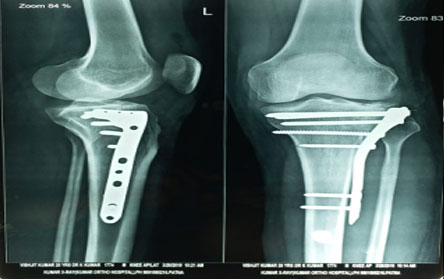

Trauma surgery:

Trauma surgery is a surgical specialty that utilizes both operative and non-operative management to treat traumatic injuries.

The Center of Orthopedics KUMAR ORTHO HOSPITAL ,Patna, offers the entire spectrum of modern orthopedic management, which is effective, patient - friendly & result oriented. In a nutshell, it is one stop treatment for all orthopedic ailments and fractures with emphasis on avoidance of complications, rapid mobilization, decreased period of confinement and an early return to normalcy.